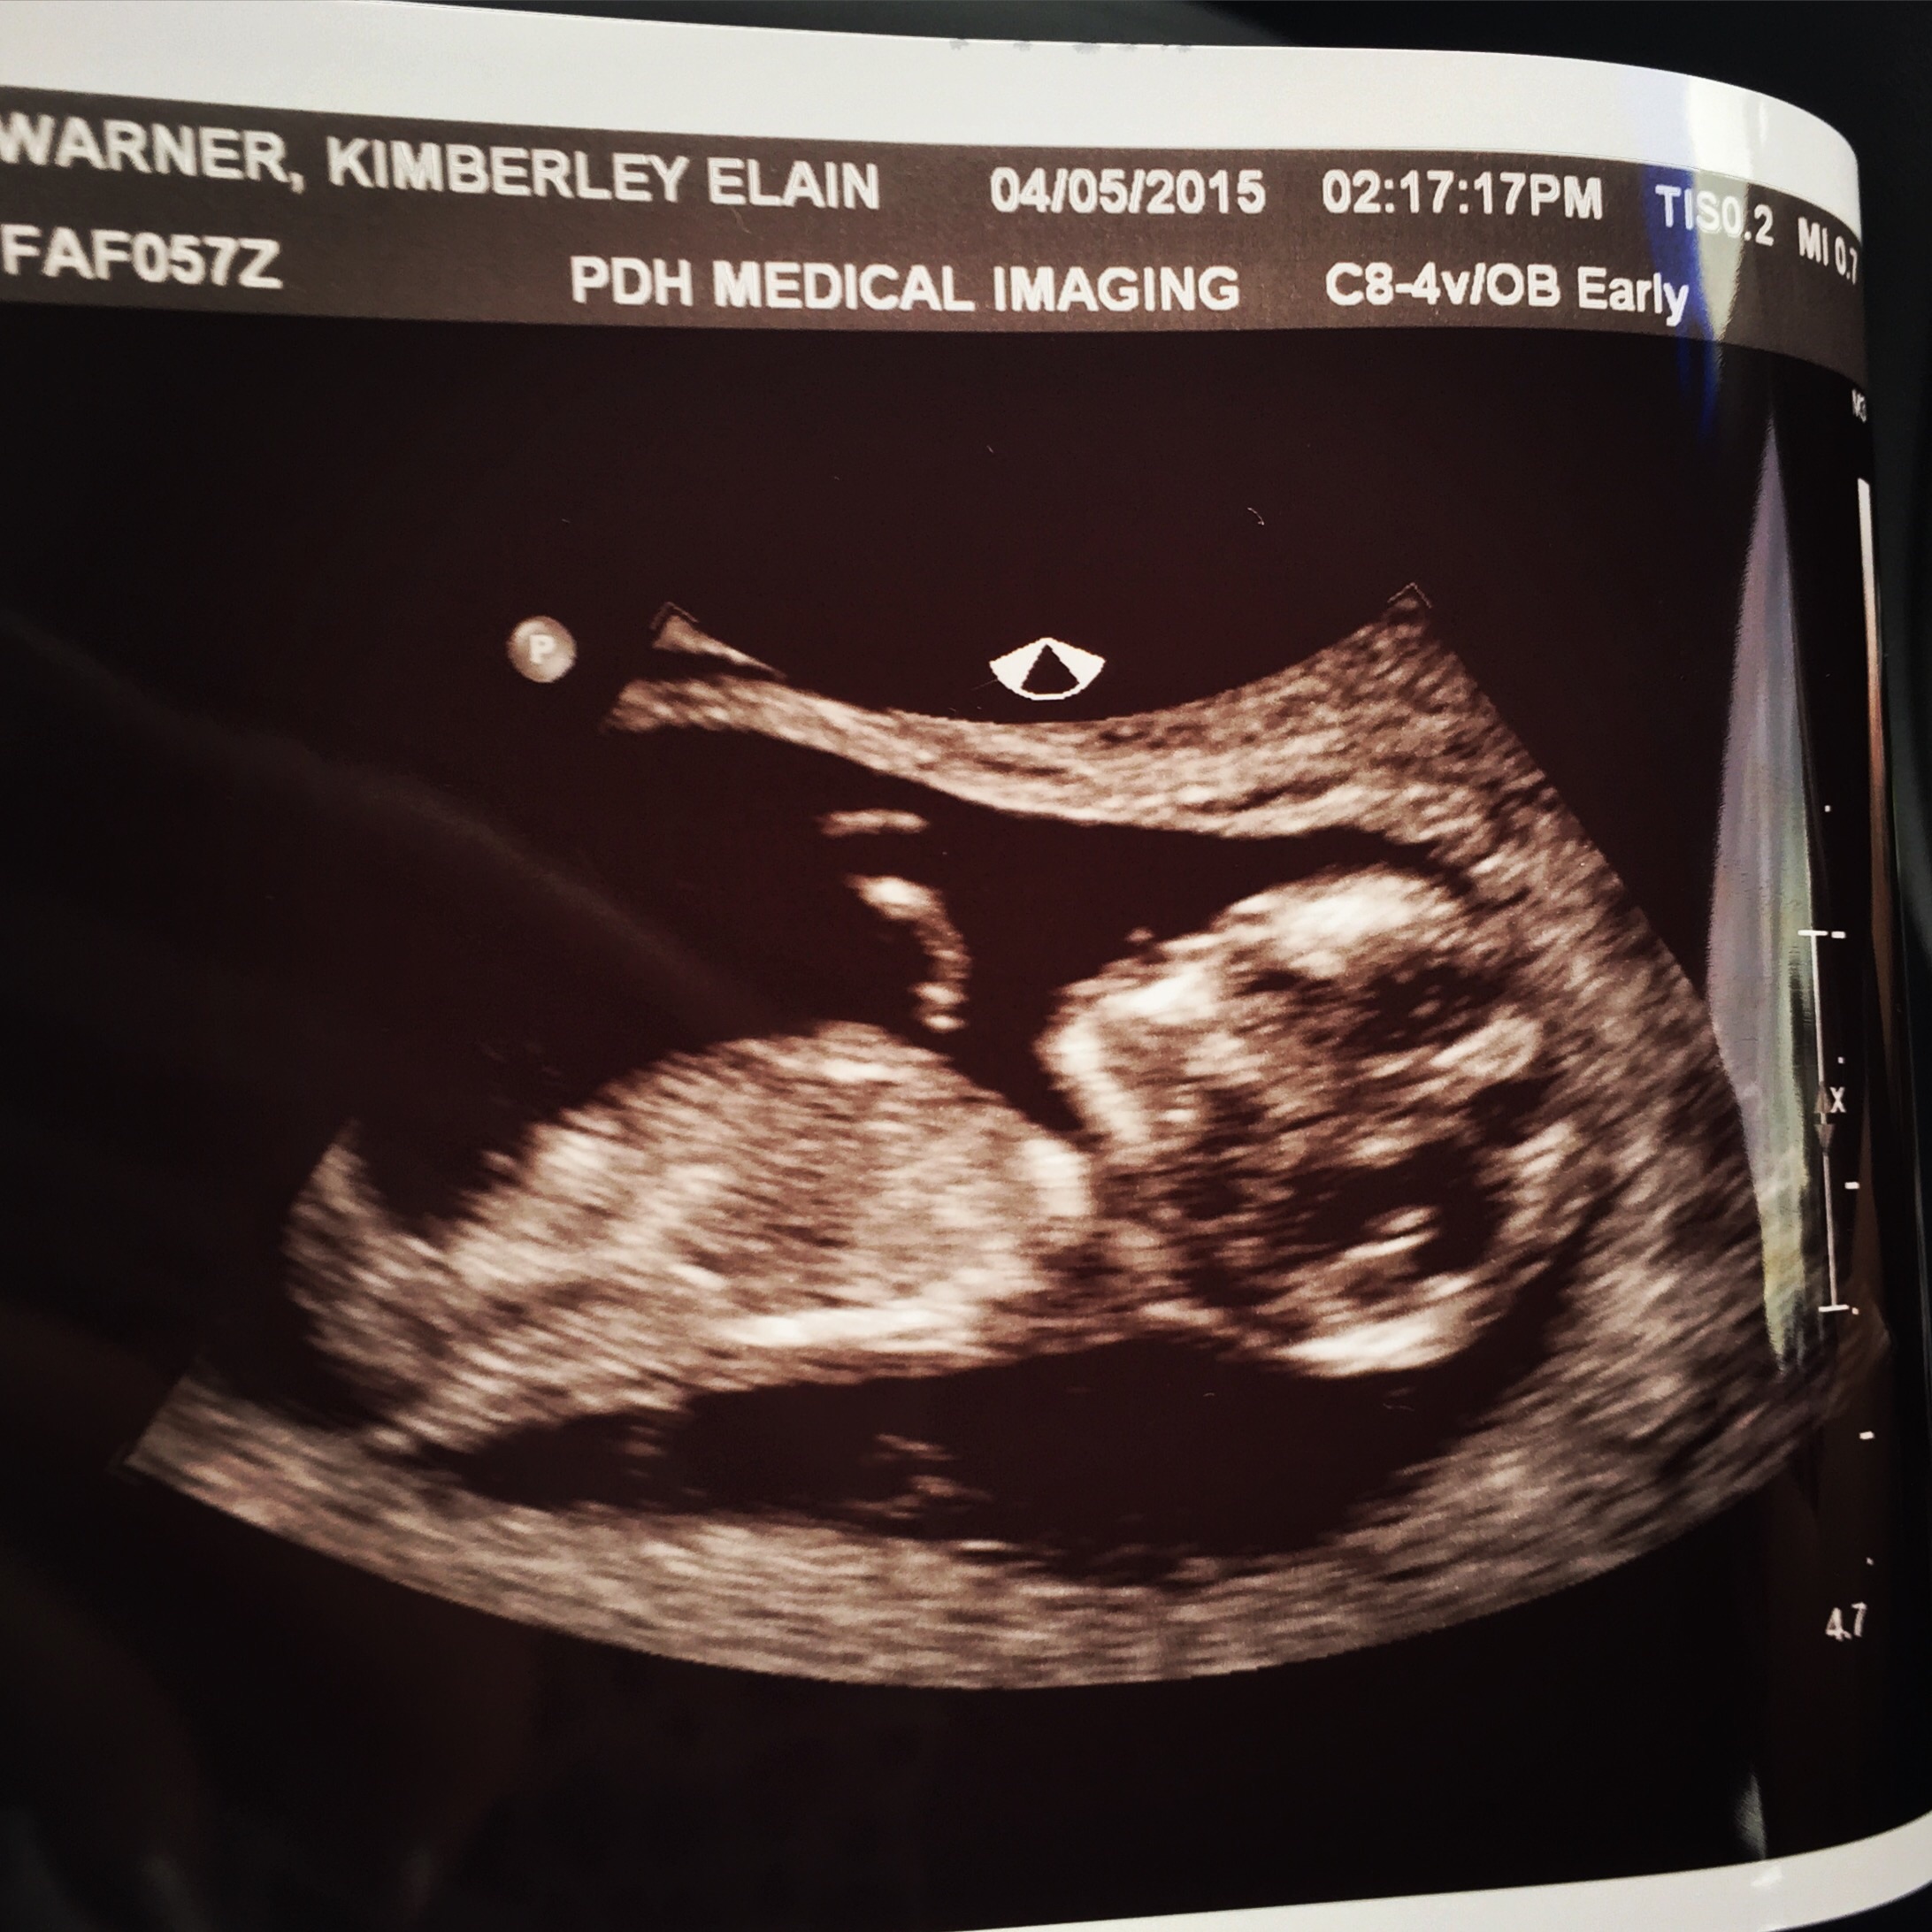

Had our first ultrasound yesterday! Found out I'm 11w2d which means I'm teetering between November/December. My due date as it stands is November 24th so right around thanksgiving It was just so surreal seeing the baby there with my DH. We were both just so happy to see a little baby there... it waved its arms a bit which was just so adorable.

Didn't catch what the heartrate was, but we definitely saw its little heart flickering Just so freaking amazing